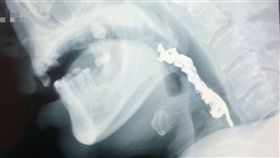

男誤吞假牙卡喉嚨 醫:切勿自行催吐

一名住在南投縣的50歲張姓男子吃晚餐時,不慎將整排假...

2018/01/16 16:49